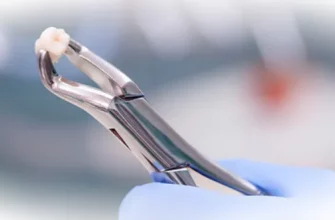

Сложное удаление зубов — это процедура, требующая внимательного